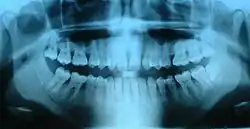

Ortopantomografía

La ortopantomografía o radiografía panorámica es una técnica radiológica que representa, en una única película, una imagen general de los maxilares, la mandíbula y los dientes. Por tanto, es de primordial utilidad en el área dentomaxilomandibular.

Su papel en el diagnóstico odontológico, no solo de los dientes sino también del maxilar y mandíbula, es fundamental. Sin la ortopantomografía, el odontólogo perdería una gran ayuda en la mayoría de las especialidades de su campo. Prácticamente, es utilizada de forma sistemática en odontología, llegando a ser un arma diagnóstica rutinaria. El valor diagnóstico de la ortopantomografía en cirugía bucal, implantología, ortodoncia, periodoncia y en patología oral y dental está claramente demostrado.

El término de radiografía panorámica es el más comúnmente utilizado, ya que la radiografía resultante muestra una visión panorámica de la cara y parte inferior de la cabeza. Laudenback describe la ortopantomografía como uno de los inventos radiológicos más originales de los últimos decenios. El 40 % de los hallazgos patológicos principales y secundarios se descubren a partir de ella. Amplía el campo de diagnóstico en un 70 % y reduce la dosis de radiación de la superficie cutánea en un 90 % con respecto a las series radiográficas periapicales.